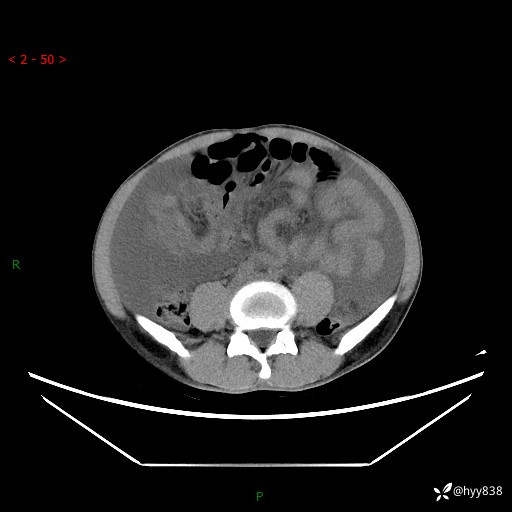

现病史:患者10天前无明显诱因出现腹部胀痛不适,无畏寒发热,无胸痛胸闷,无心慌气短,无恶心呕吐,无腹泻及黑便,无粘液血便及里急后重等症状,4天前在当地县人民医院就诊,行腹部CT示:下腹部占位性病变,腹腔及盆腔积液;今患者为求进一步诊治来我院治疗,门诊以“腹水”收治入院。 发病以来,精神饮食可,大小便正常,体重体力无明显变化。

腹部CT平扫+增强